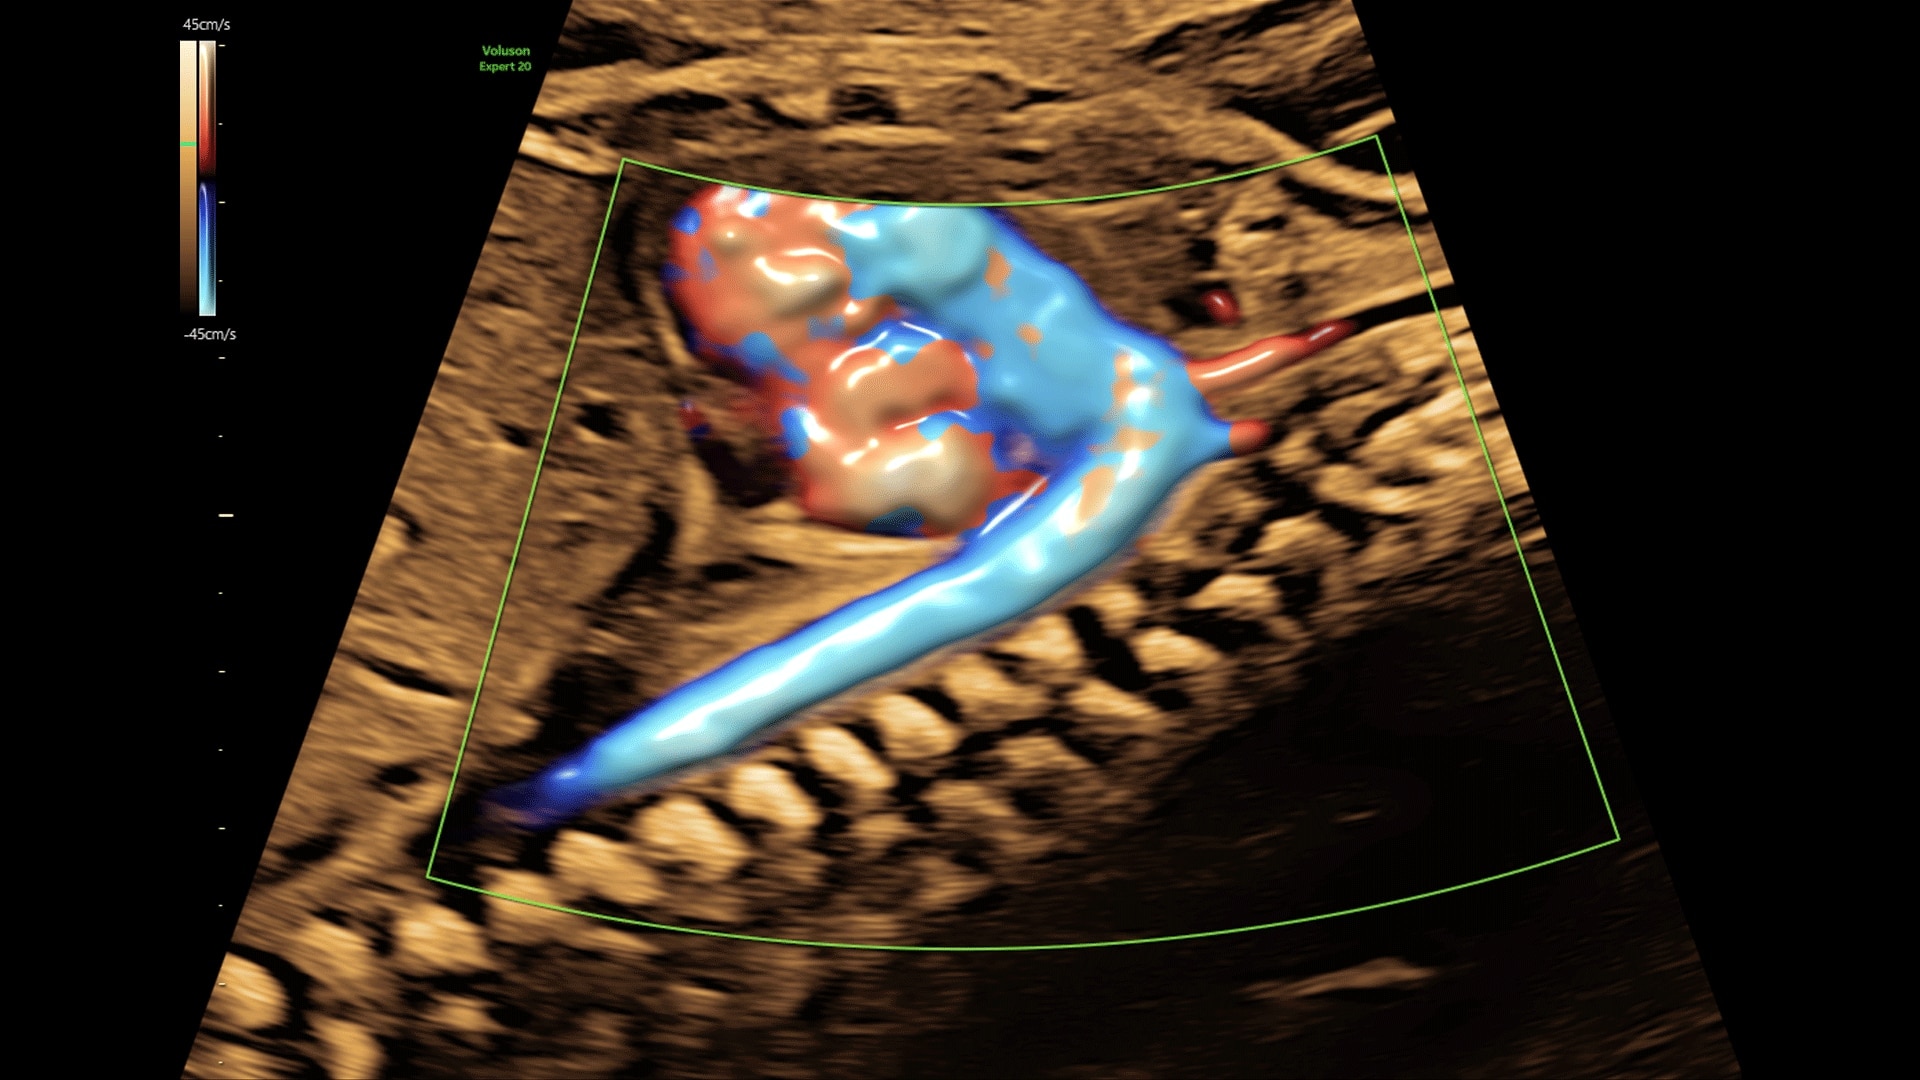

Generate spectacular 2D/3D and color Doppler images with increased penetration and stunning clarity, to help visualize critical details needed for diagnostic assurance. The Lyric Architecture unlocks new imaging and processing power to expand your imaging capabilities for years to come